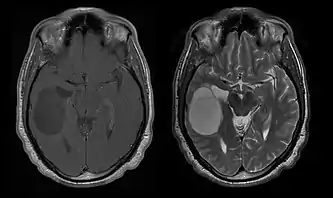

La tomodensitométrie (TDM) et L'imagerie par résonance magnétique (IRM) peuvent détecter efficacement une néoplasie dans le cerveau. L'IRM est plus sensible que la TDM pour identifier les lésions, mais présente des contre- indications pour les patients porteurs de stimulateurs cardiaques, de prothèses incompatibles, de clips métalliques et contre-indications. La TDM reste la méthode de choix pour détecter les calcifications au sein des lésions ou les érosions osseuses de la calotte ou de base du crâne. L'utilisation d' agents de contraste, iodés dans le cas du scanner et paramagnétiques (gadolinium) dans le cas de l'IRM, permet l'acquisition d'informations sur la vascularisation et l'intégrité de la barrière hémato-encéphalique, une meilleure définition de la tumeur tumorale par rapport à l' œdème environnant et à la génération d' hypothèses sur le degré de malignité. L'examen radiologique permet également d'évaluer les effets mécaniques et les modifications importantes des structures cérébrales résultant de la tumeur, telles que l' hydrocéphalie et les hernies, dont les effets peuvent être fatals. Enfin, en préparation à la chirurgie, ce diagnostic peut être utilisé pour déterminer la localisation de la lésion ou l'infiltration de la tumeur dans des zones vitales du cerveau. À cette fin, l'IRM est plus efficace que la tomodensitométrie car elle peut fournir des images en trois dimensions.

Les outils d'imagerie radiologique diagnostique mettent en évidence la modification du tissu néoplasique par rapport au parenchyme cérébral normal (par le biais de modifications de la densité tissulaire imagée électroniquement en TDM et de l'intensité du signal en IRM). Comme la plupart des tissus pathologiques, les tumeurs sont également reconnaissables par une accumulation accrue d'eau intracellulaire. Dans la tomodensitométrie, ils apparaissent hypodenses, c'est-à-dire de moindre densité que le parenchyme cérébral, dans la tomographie par résonance magnétique nucléaire avec relaxation spin-réseau hypointense et en relaxation spin-spin ainsi que l' hypersignal en pondération protonique (PD).

La tomodensitométrie du cerveau montre généralement une masse tissulaire qui peut être améliorée par l'un ou l'autre contraste. Au scanner, les gliomes de bas grade apparaissent généralement isodenses au parenchyme normal et peuvent donc ne pas présenter de rehaussement de contraste. De même, les lésions de la fosse crânienne postérieure sont difficiles à identifier au scanner. Par conséquent, les seuls résultats d'une telle tomographie ne sont pas toujours suffisants à des fins diagnostiques. Dans les cas douteux, l'utilisation de l'imagerie par résonance magnétique plus sensible est indispensable.

Sur-L'IRM montre une tumeur intracrânienne comme une lésion massive qui peut devenir plus luminescente après utilisation du produit de contraste. Cependant, il y a toujours une anomalie de signal dans -L'imagerie par résonance magnétique, qui indique la présence d'une néoplasie ou d'un œdème vasogénique. Habituellement, une luminescence accrue (amélioration du contraste) indique une tumeur d'un grade supérieur de malignité. Un anneau de contraste est caractéristique du glioblastome, avec la partie luminescente correspondant à la partie vitale de la tumeur maligne, et la plus foncée - zone hypointense correspondant à une nécrose tissulaire.

Les astrocytomes diffus II apparaissent sur la tomodensitométrie. Grades que les lésions moins intenses. Dans l'imagerie par résonance magnétique préférée, les agents de contraste peuvent ne pas être en mesure de mettre en évidence ces néoplasmes, leur luminescence peut être plus fine et plus faible. Un plus intense peut indiquer des tissus d'anaplasie accrue. Dans la mesure du possible, une biopsie est suggérée pour obtenir des échantillons de la partie anaplasique de la tumeur.

En règle générale, les patients atteints d'astrocytome anaplasique présentent des crises d'épilepsie, des déficits neurologiques focaux, des maux de tête et des changements de personnalité. L'âge moyen des patients est de 45 ans. L'imagerie par résonance magnétique montre généralement une lésion massive avec un signal de contraste accru, qui peut aussi être plus faible. Le diagnostic repose sur l'examen histologique de la lésion par biopsie ou résection chirurgicale.

L'IRM montre généralement une lésion de contraste massive impliquant le cervelet. Comme mentionné ci-dessus, le médulloblastome a une forte propension à infiltrer localement les leptoméninges ainsi qu'à se propager à travers l'espace sous-arachnoïdien, impliquant les ventricules, la convexité cérébrale et les surfaces leptoméningées de la colonne vertébrale. Par conséquent, il est nécessaire de mettre en résonance tout l'axe crânio-spinal.

Les patients souffrent d'une variété de symptômes caractéristiques d'une lésion massive focale ou multifocale. L'IRM montre généralement des tumeurs avec un rehaussement de contraste homogène au sein de la substance blanche périventriculaire profonde. La multifocalité et le rehaussement inhomogène sont typiques des patients dont le système immunitaire est affaibli. L'analyse du lymphome du SNC est extrêmement importante dans le diagnostic différentiel de la néoplasie cérébrale. Il est à noter que l'administration de corticoïdes peut entraîner la disparition complète du rehaussement, rendant difficile le diagnostic des lésions. Par conséquent, si un lymphome du SNC doit être pris en compte dans le diagnostic différentiel, les corticoïdes doivent être évités à moins que l'effet de masse ne provoque un problème grave et immédiat chez le patient.